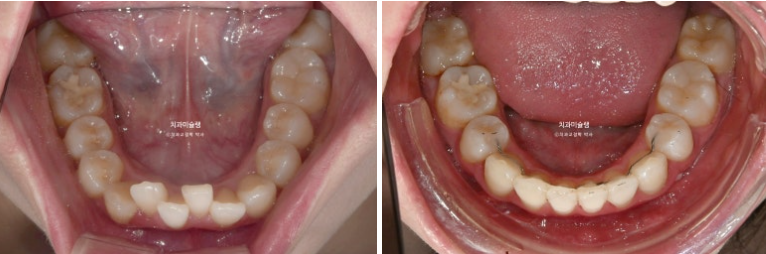

이제 전후 비교 보겠습니다.

파란 화살표 큰어금니가 입천장쪽으로 들어오면서 가위교합이 해소가 되었습니다.

예쁜 배열위에 고정식 철사 유지장치까지 붙은 모습입니다.

어긋나 있던 중심선은 정확히 맞으며 깊게 물리는 과개교합이 해소되어 이제 아래 앞니가 정상적으로 보입니다.

뿐만 아니라 치아 높낮이 불규칙으로 인해 들쑥날쑥 했던 아래 앞니가 배열되면서 잇몸라인도 어느정도 정리가 되었습니다.

파란 화살표 부분의 가위교합이 개선이 되면서 어금니 교합은 물샐틈 없는1급 교합관계를 보입니다.